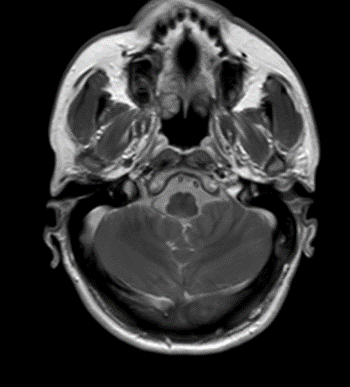

Se solicitó inicialmente Imagen de resonancia magnética (IRM) de columna lumbosacra simple y estudios de neurofisiología. La electromiografía más neuroconducciones de las 4 extremidades reportó neuropatía mielínica de expresión leve del nervio peroneo motor. Imagen de resonancia magnética lumbosacra simple muestra hallazgos compatibles con aracnoiditis adhesiva (figura 1). Ante estos hallazgos, se complementan estudios con resonancia torácica y cerebral con contraste. En la resonancia de columna torácica, se observa incipiente siringomielia (figura 2.) y la resonancia cerebral con contraste no mostró alteraciones.

Figura 1.